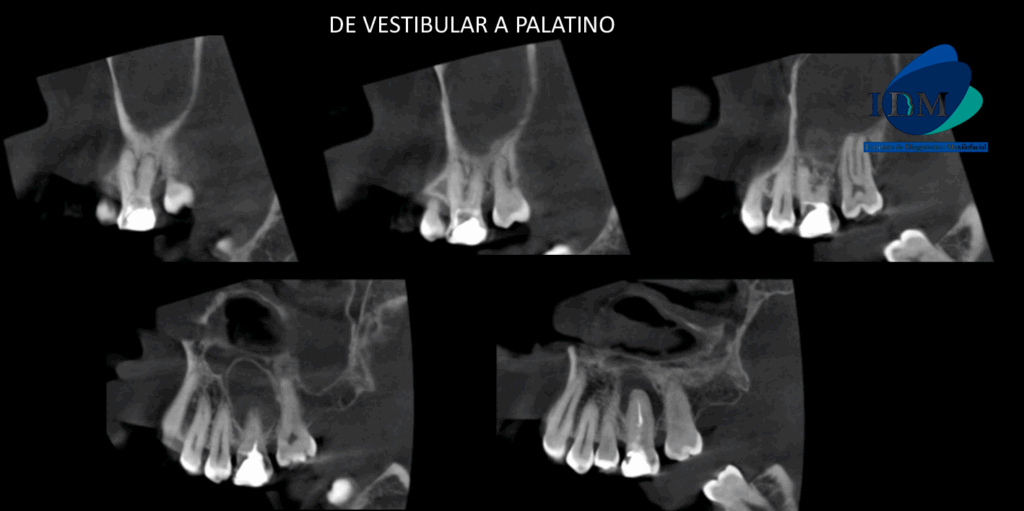

A la evaluación de la tomografía computarizada en cortes axiales, transaxiales y tangenciales se observa la pieza 16 con la raíz mesiovestibular con una obturación parcial y sobre extendida del conducto, asimismo presenta un conducto colateral obliterado y un proceso osteolítico periapical y reabsorción radicular externa del tercio apical; la raíz distovestibular presenta también una obturación parcial de conducto y la raíz palatina presenta un espigo intrarradicular, obturación parcial y subextendida del conducto y una imagen hipodensa corticalizada que desplaza hacia cefálico el piso de seno maxilar y compromete la tabla ósea palatina compatible con quiste radicular, asimismo ocasiona un engrosamiento de la mucosa antral ipsilateral compatible con sinusitis de origen odontogénico.

CORTES TANGENCIALES

CORTES TRANSAXIALES